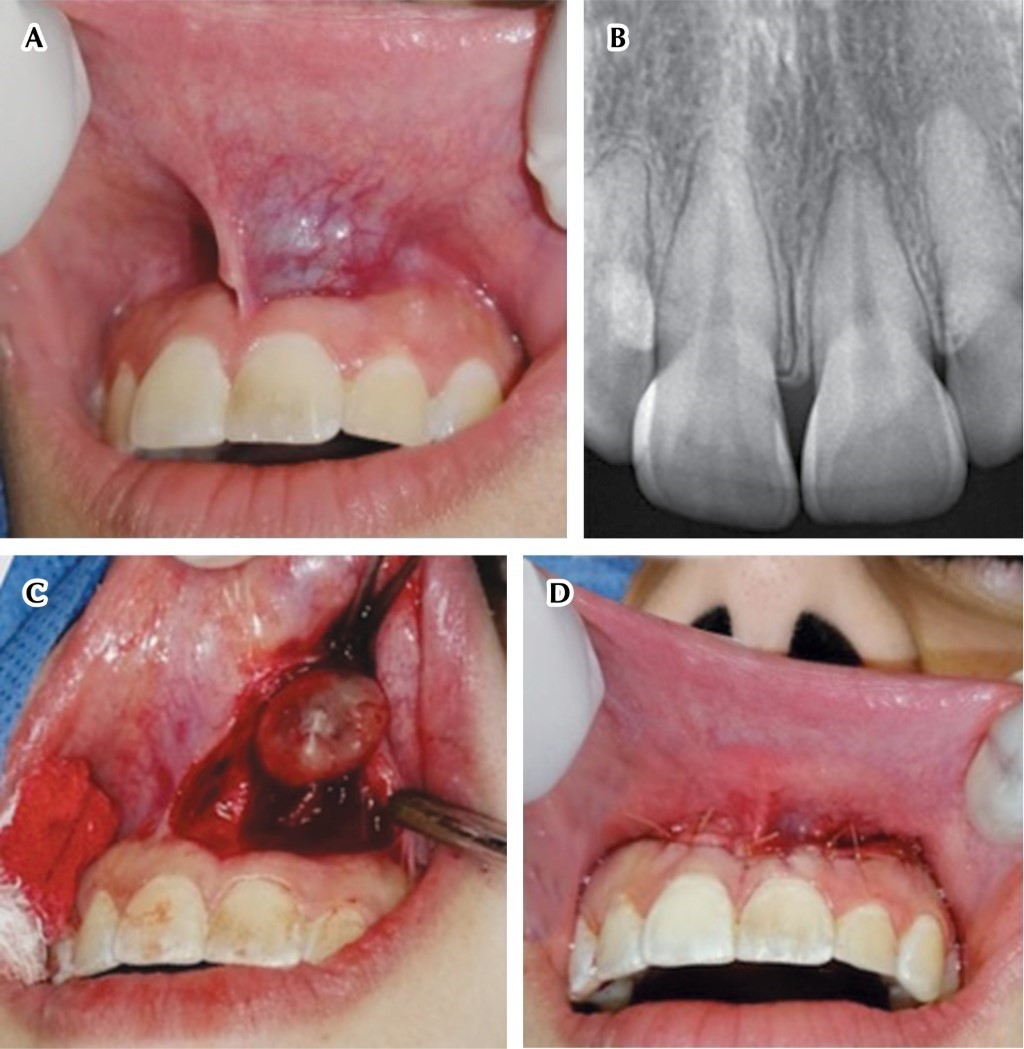

Angioleiomyoma in the oral cavity ''a rare neoplasm in an unusual site''. Case report and literature review.

The angioleiomyoma (AL) is a benign neoplasm, well circumscribed and slow growing, that represents 5% of the soft tissue neoplasms, whose etiology is unknown. It originates from smooth muscle, mostly from the walls of blood vessels; regarding its location, it more frequently appears in the extremities, being rare in the head and neck region, and even more so in the oral cavity. Histologically, the lesion is characterized by being a well encapsulated nodule with proliferation of mature smooth muscle bundles around the lumen of the blood vessels, whose cells are usually positive for immunohistochemical markers such as alpha smooth muscle actin, desmin, HHF35, myosin, calponin and H-caldesmon. The current treatment is complete surgical excision having zero recurrence rate. The objective of the following article is to educate on the importance of correct diagnosis and management of intraoral lesions through the presentation of a clinical case of a vascular leiomyoma located in the nasolabial region, in addition to reviewing the corresponding literature.

Figure 1

Figure 2